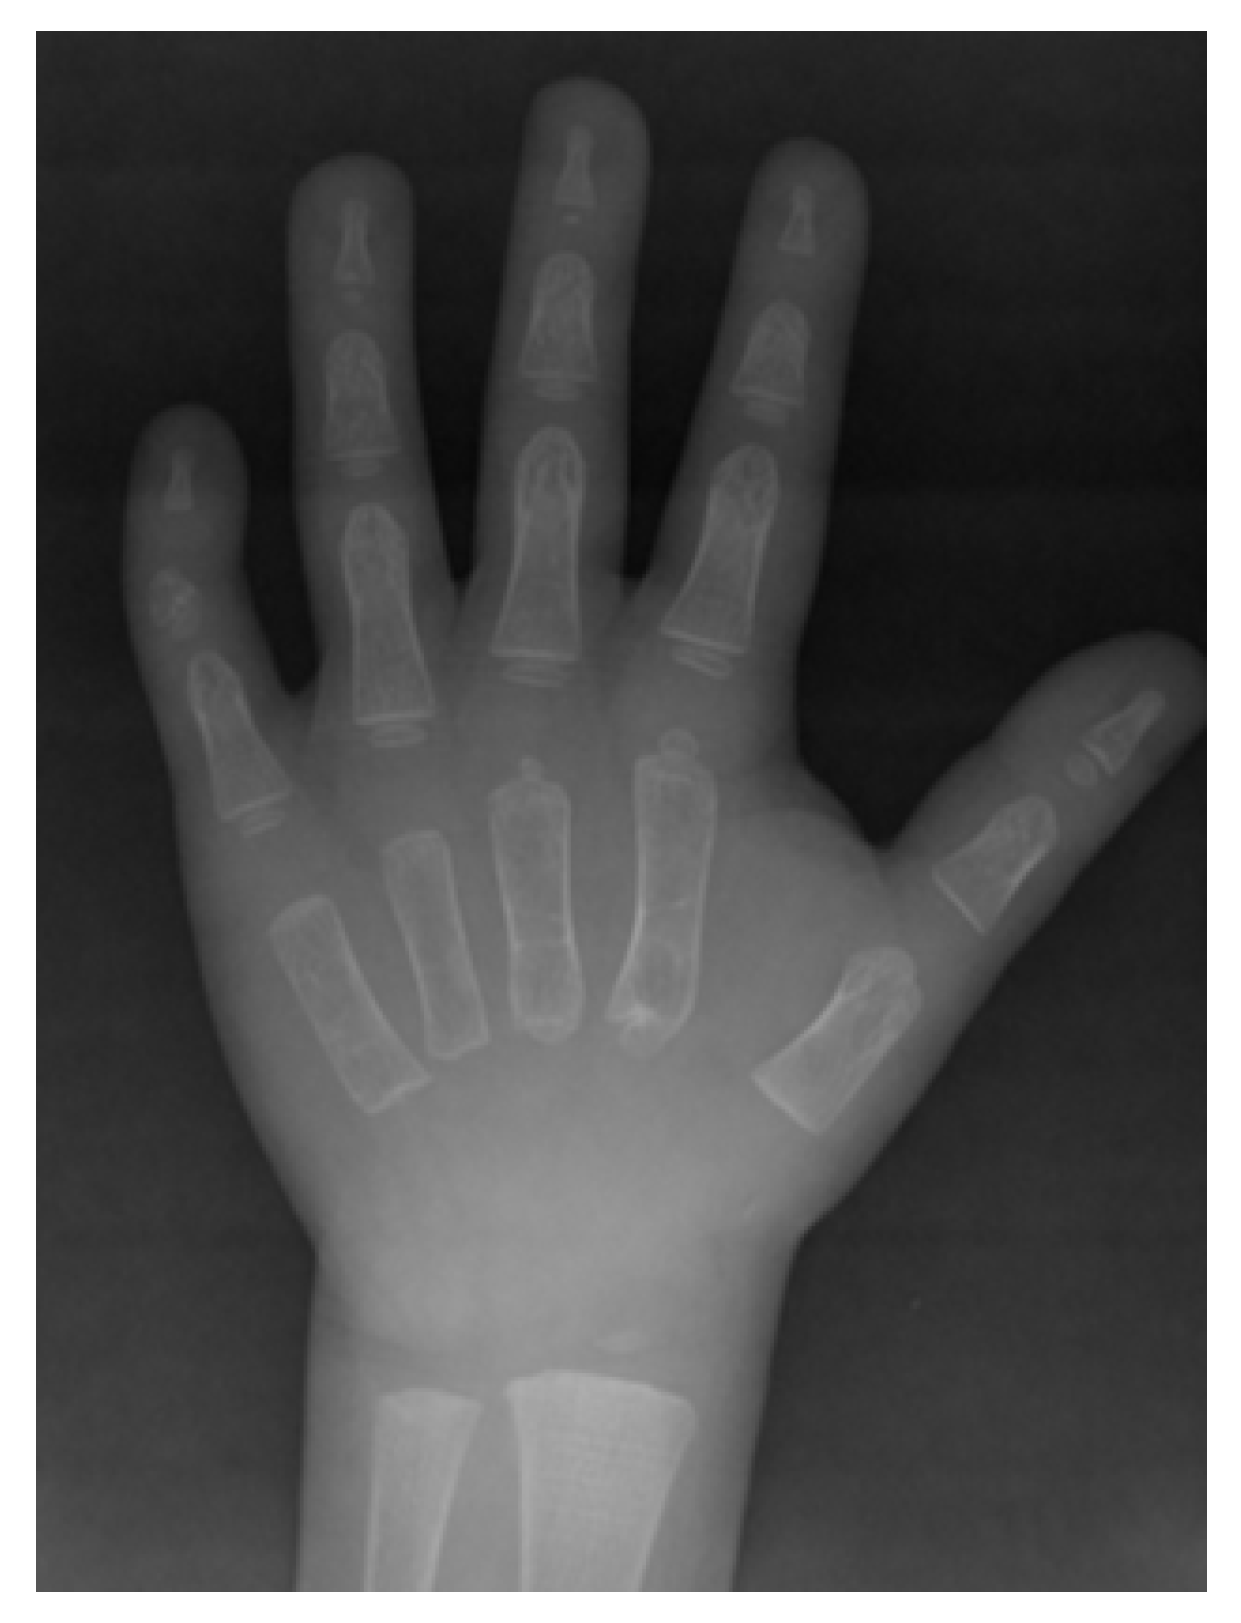

2.1. Clinical Data